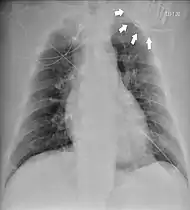

Chest radiograph showing twiddler's syndrome. The leads of the automated external defibrillator are wrapped around the device and can't be seen in the ventricle. | |